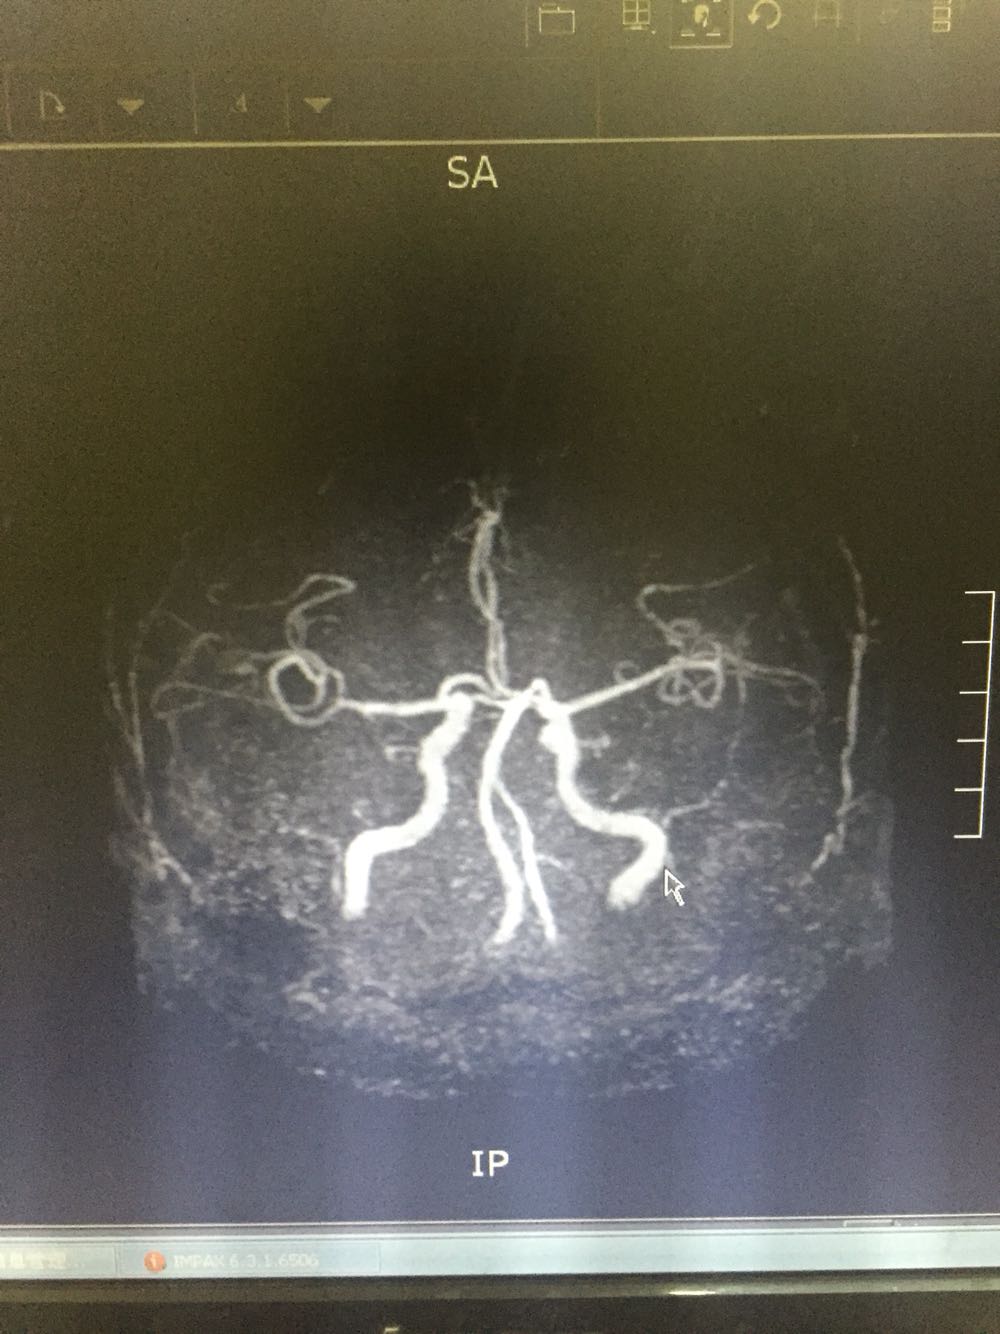

76岁女患,因眩晕三小时入院 既往高血压3年,冠心病史 该患者于入院前三小时无明显诱因出现眩晕,伴有恶心、头痛,无呕吐,病程中无肢体活动障碍,无言语不清,无意识障碍及尿便失禁,不伴有耳鸣及听力减退,为求进一步诊治而来我院。 血、尿化验未见明显异常

诊断:脑梗死、高血压 治疗:改善循环、抗血小板聚集、营养神经、调控血压对症治疗

主要注意与基地动脉尖综合症相鉴别。该患者右侧P2及左侧P3段局限性狭窄